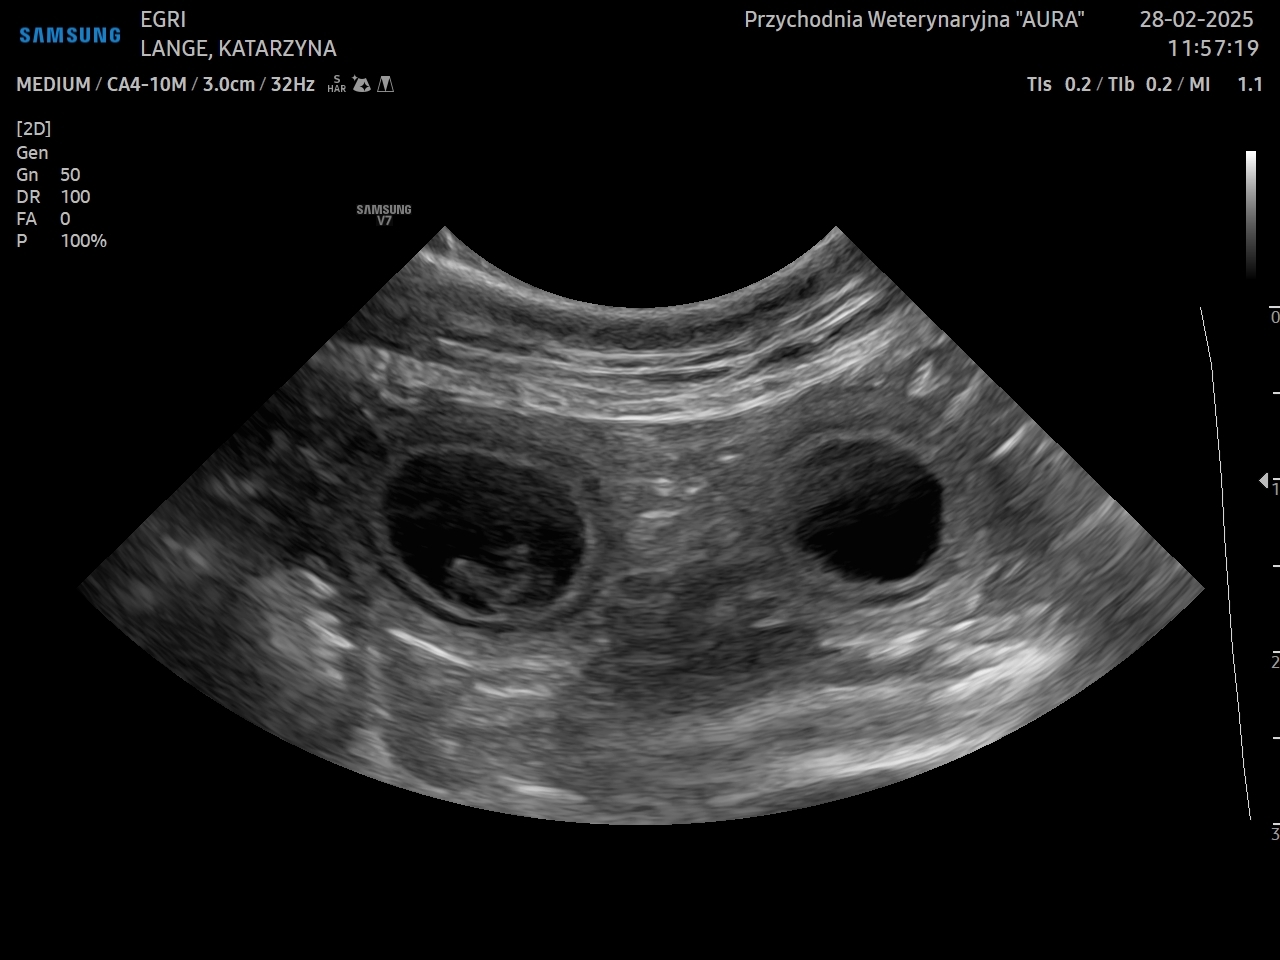

POTWIERDZILIŚMY CIĄŻE NASZYCH SUCZEK

Jest nam niezmiernie miło poinformować, że potwierdziliśmy ciąże u Egri i Vistuli!

Te dwie ciąże są dla nas niezwykle ważne i cenne. Bardzo czekaliśmy na informację czy się udało i JEST!

Szczeniaki urodzą się na początku kwietnia 2025.